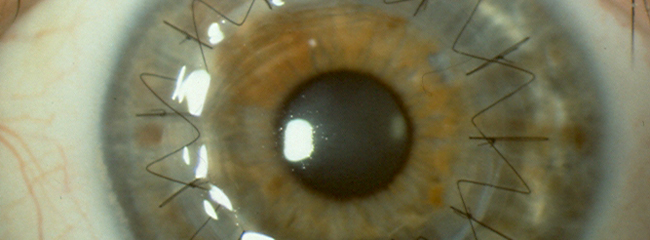

Trabajan con tres modelos. El más avanzado se basa en una matriz artificial de fibrina y agarosa. La agarosa se extrae de las algas y es biocompatible, y la fibrina del plasma humano –la parte que forma el coágulo se obtiene de un donante. Esta mezcla forma un gel donde la colocan las células de córnea humana, que cultivan en el laboratorio para conformar el tejido artificial. Ya han realizado experimentos en animales y cuando se observó que era óptimo y que iba bien, iniciaron la fase de reclutamiento de pacientes.

El prototipo de fibrina y agarosa es pionero en ensayos clínicos a nivel mundial

Actualmente este ensayo clínico está focalizado en una patología realmente severa y que no tiene un tratamiento eficaz como es la úlcera corneal de tipo trófico. Pero esto nos abre puertas a pensar que el futuro esta cerca.

Su misión será ayudarle a evolucionar la queratoprotesis que el doctor Dohlman ha desarrollado allí. Se trata de un dispositivo hecho de metacrilato que ayudaría a que la luz pase por el ojo.